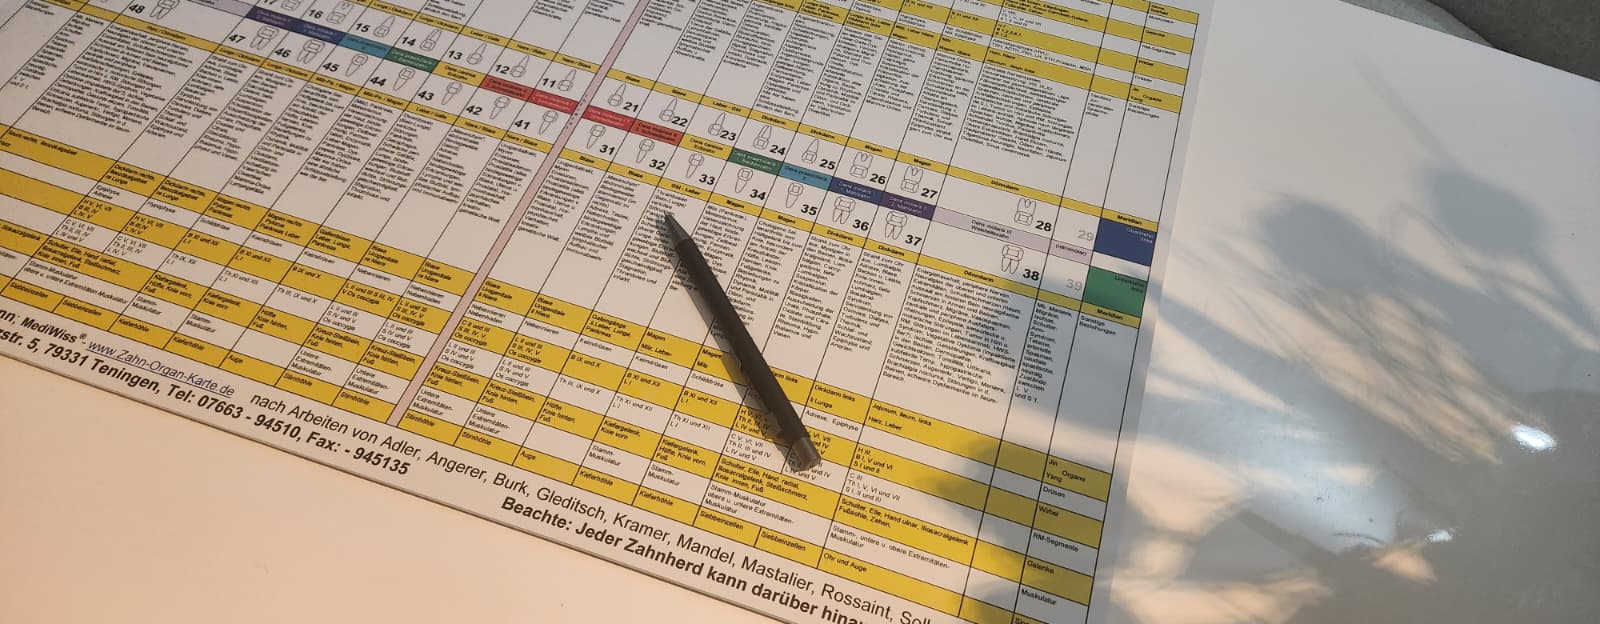

Jeder einzelne Zahn steht über Meridiane, Nervenbahnen und Blutgefäße in direkter Verbindung zu bestimmten Organen. Ein erkrankter oder abgestorbener Zahn kann sich daher in Beschwerden im zugeordneten Organbereich äußern. Umgekehrt können Entzündungen oder funktionelle Störungen eines Organs Auswirkungen an dem entsprechenden Zahn zeigen.

Zahn 24 (vorderer Backenzahn im linken Oberkiefer) gehört zum Funktionskreis Lunge/Dickdarm.

Dieser Funktionskreis gilt als besonders empfindlich gegenüber Themen wie Trauer, Schuldgefühlen und dem Nicht-Loslassen-Können.

Zahn 24 kann zeigen, wie solche emotionalen Prozesse die Fähigkeit beeinträchtigen, Veränderungen anzunehmen. Gerade bei Patienten mit nächtlichem Knirschen oder Pressen und Läsionen im Bereich der kleinen Backenzähne sollte dieser Zusammenhang genau betrachtet werden.

Zahn 24 symbolisiert unsere Fähigkeit, Veränderungen anzunehmen und loszulassen. Sowohl aus physischer als auch aus psychischer Sicht haben unsere Zähne damit einen großen Einfluss auf die Regulationsfähigkeit des Organismus.